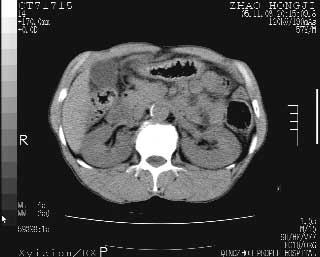

临床资料:男性,57岁,上腹部疼痛并5天,突然加重并延及全腹伴恶心5小时入院。胰淀粉酶化验在正常范围。检查:腹肌紧张,全腹压痛、反跳痛,尤以右上腹部为著。肠鸣音减低。血常规:wbc14.6x10/9, n:11.3x10/9 ,血压:135/90mmhg. 胸部透视:腹部肠腔轻度张气,未见其它异常改变。

从图提示我同意空腔脏器穿孔的诊断,来源肠道{由于病程较短,故没能见到肠系膜聚局的征象}。

肝缘见少许气体,胰尾部见少许气体包饶(蓝色圈),12指肠上部或球部邻近胆囊周边也可见少许气体影(黄色圈),并忖托出胆囊壁,12指肠远段肠道内未见明显气体(白色箭)。

消化道穿孔。12指肠球部周和胰周积气考虑12指肠穿孔可能性大。

腹腔内脂肪影密度增高,考虑腹膜炎

入院3小时后行剖腹探查术,见腹腔内大量脓性混浊液约1000ml,十二指肠球部溃疡穿孔,溃疡面约2.5x2cm,穿孔直径约0.6cm。胃内容物外益,周围组织炎性水肿明显。行十二指肠穿孔修补术。术后诊断:

1、十二指肠溃疡穿孔

2、弥漫性腹膜炎

对于少量的腹腔游离气体,ct检查较普通透视有绝对的优势,它不仅可以看到肝脏前上缘的气体,而且还能够看到小网膜区的游离气体。从而可以肯定诊断。各位分析战友的很好,感谢大家的参入!